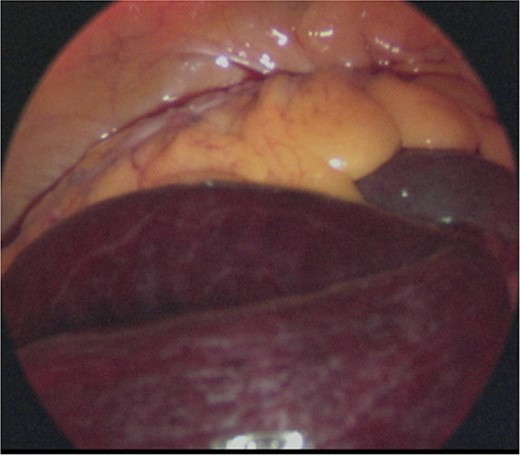

A laparoscopic approach was initiated, which revealed necrosis of the small bowel (Fig. 3). Because the intestinal dilatation was severe, the procedure was converted to a laparotomy to better visualize the abdominal cavity. The abdomen was opened through a median abdominal incision. Most of the small intestine was located on the dorsal aspect of the right mesocolon, and a 6-cm hernial orifice was noted at the fusion defect between the right mesocolon and retroperitoneum. Intestinal necrosis was observed in 80 cm of the ileum in the abdominal cavity outside the hernial sac. No intestinal necrosis was apparent in the small intestine within the hernial sac (Fig. 4a). The hernial sac was 12 × 6 cm in size (Fig. 5). The duodenum did not form a horizontal leg and ran caudally from the descending leg in the hernial sac to the jejunum (Fig. 6). There was no Ladd ligament or band formation. The patient was diagnosed intraoperatively with a strangulated bowel obstruction due to a right PDH with malrotation. Intestinal necrosis involved 80 cm of the ileum in the abdominal cavity outside the hernial sac. A partial resection of the necrotic jejunum was performed. After partial resection of the necrotic ileum, all intestines in the hernial sac were replaced in the abdominal cavity. The hernial sac was resected, and the hernial orifice was closed with suture. Because the ascending colon was in the normal anatomic position, no fixation procedure was performed. The total operative time was 197 min, and the estimated blood loss was 800 ml, including ascites fluid. The postoperative course was uneventful, and she was discharged on postoperative Day 10. The patient reported no abdominal discomfort after 7 months of follow-up.

Intraoperative image. Laparoscopic examination of the abdominal cavity shows necrosis of the small bowel.